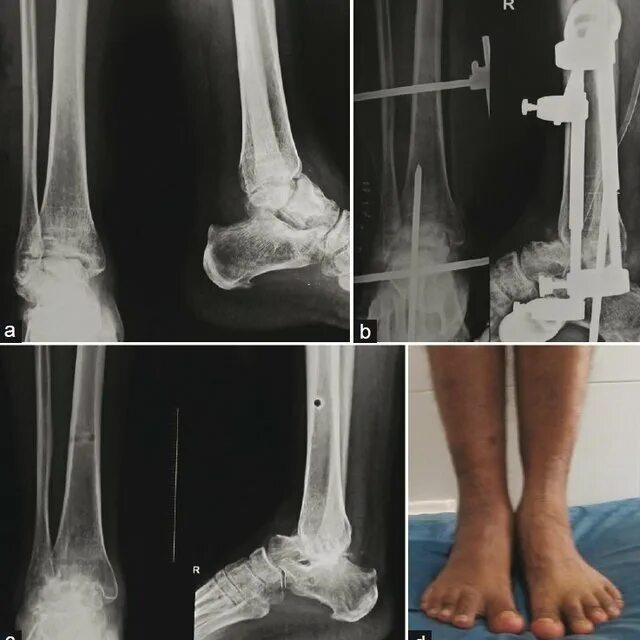

После остеосинтеза лодыжек